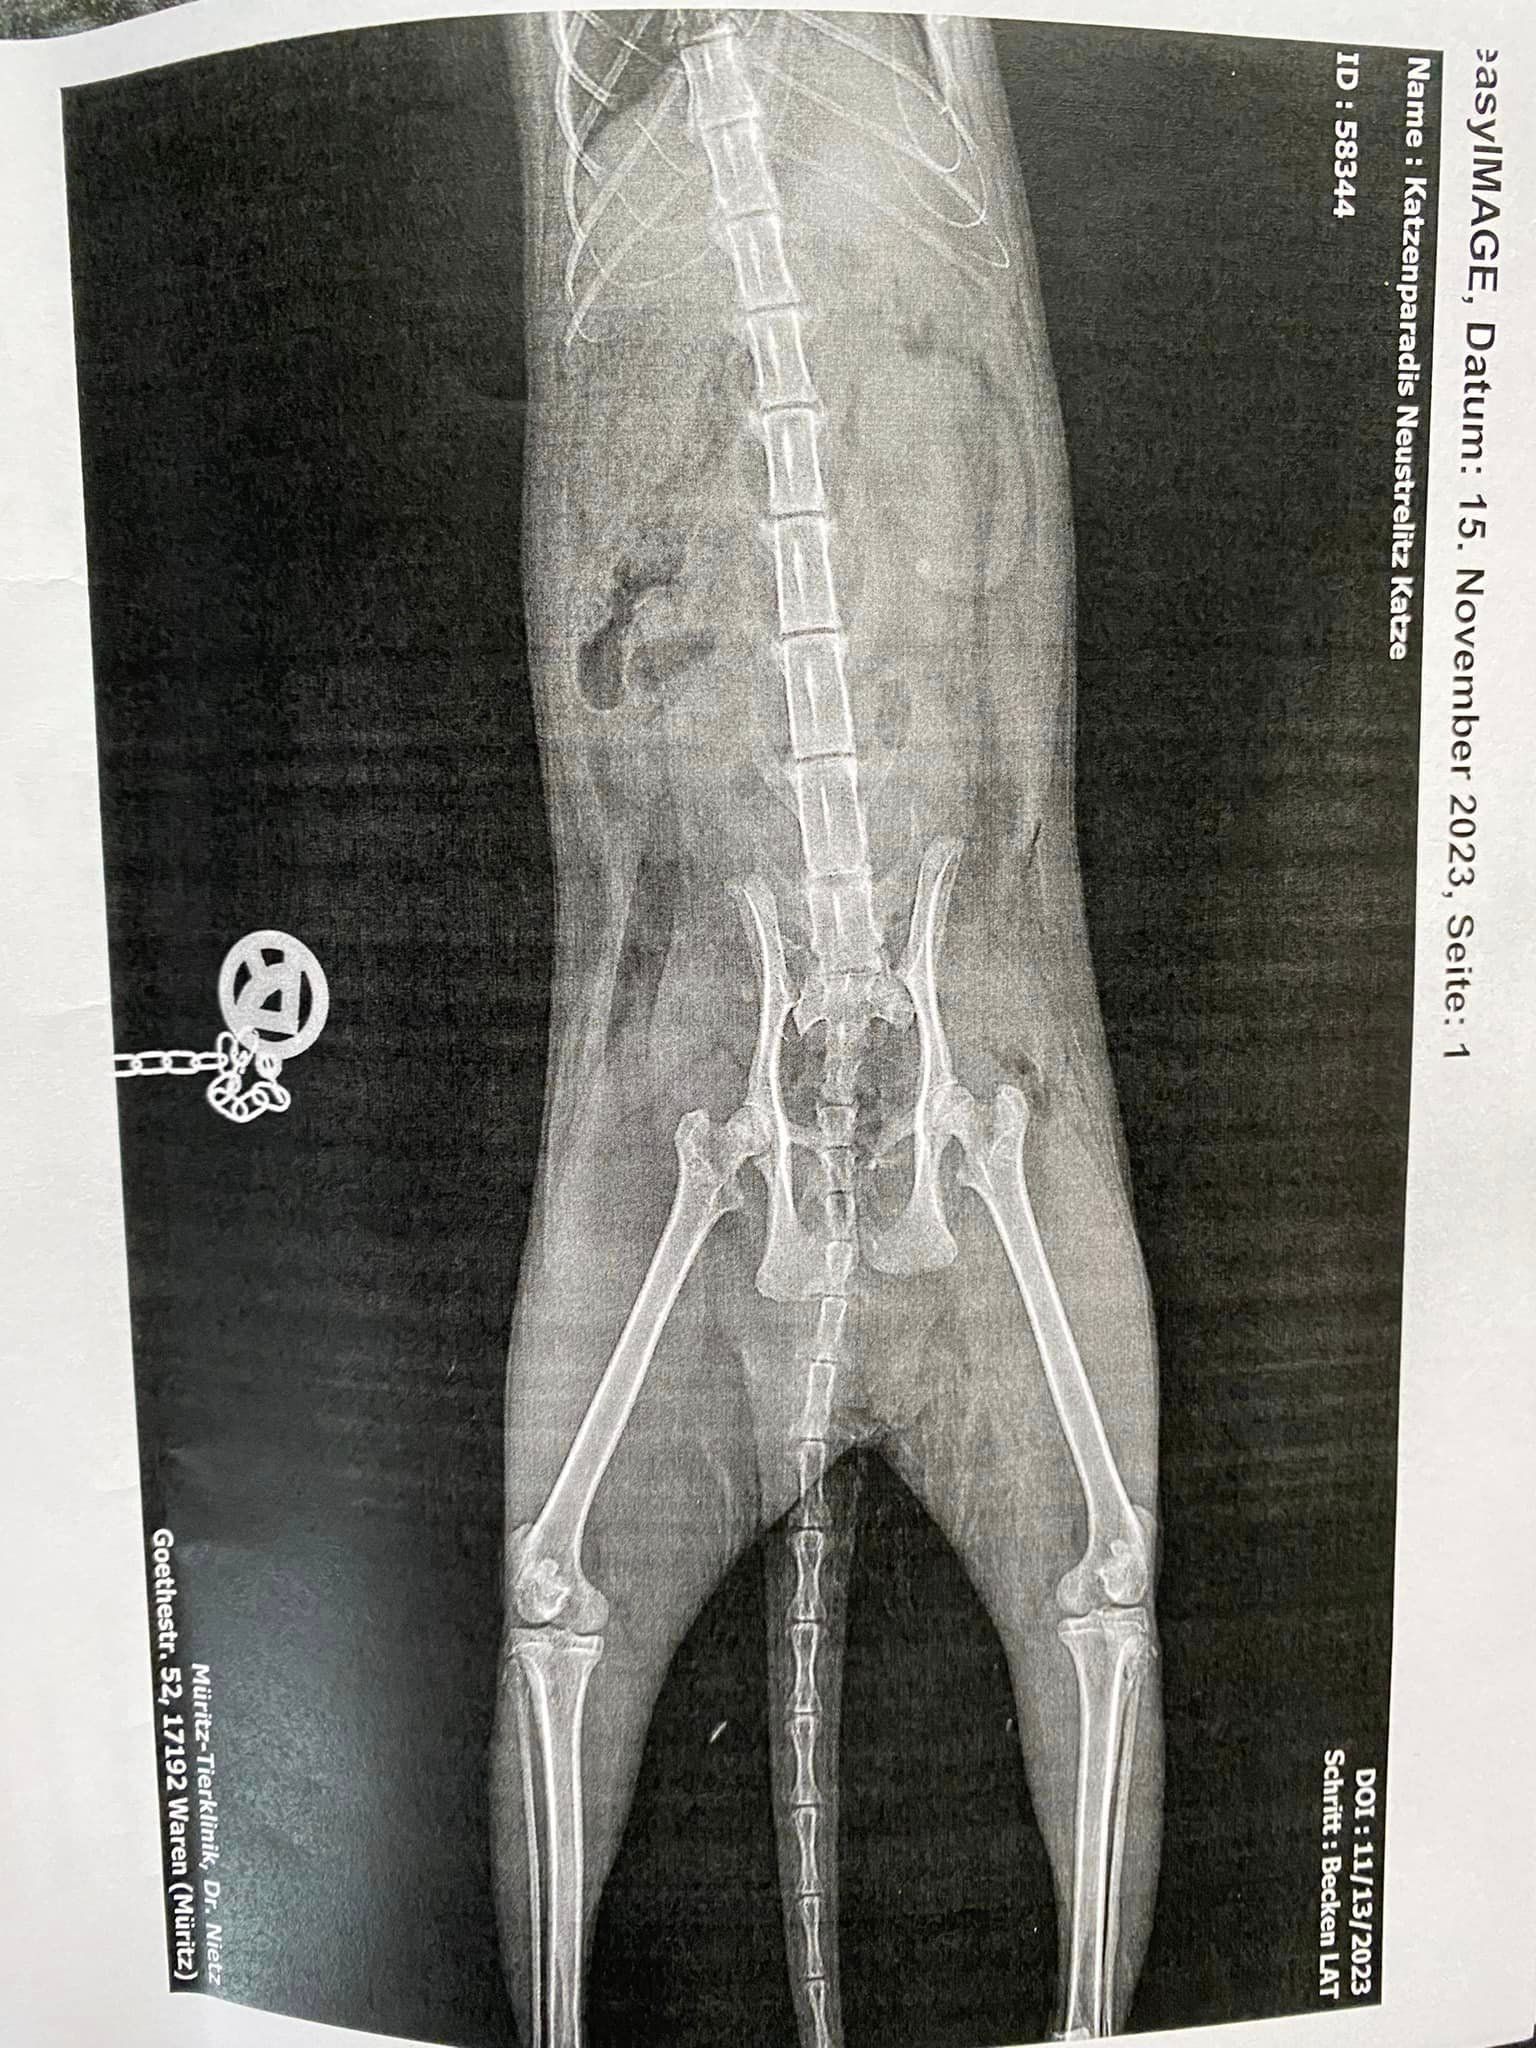

Greta hat die OP gut überstanden!

Unsere Greta hat die OP gut überstanden.

Jetzt bleibt zu hoffen, dass sie wieder lernt aufzustehen. Sie hatte zudem starke innere Blutungen und die Köpertemperatur war nicht im Normbereich.

Wir belassen sie die nächsten 10 Tage noch in der Obhut der Klinik. Dort wird ihr alles zuteil, was sie benötigt inkl. Physiotherapie.

Anliegend die OP-Rechnung in Höhe 1.075 Euro. Die nächste Zahlung erfolgt bei Abholung in Höhe 720 Euro.